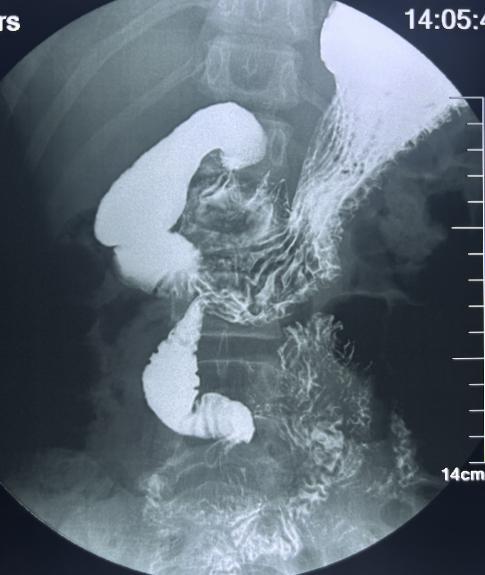

· 上消化道造影:能显示十二指肠位置异常、空肠位于右侧腹部等特征性表现

1.jpg